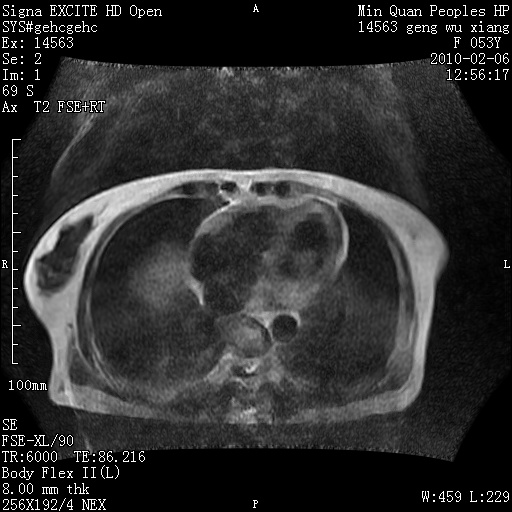

标题: MRI2762:胆道梗阻原因?

f,53y,全身黄染多日。

高位胆道梗阻 胆管癌可能性大

支持 高位胆道梗阻 胆管癌可能性大。